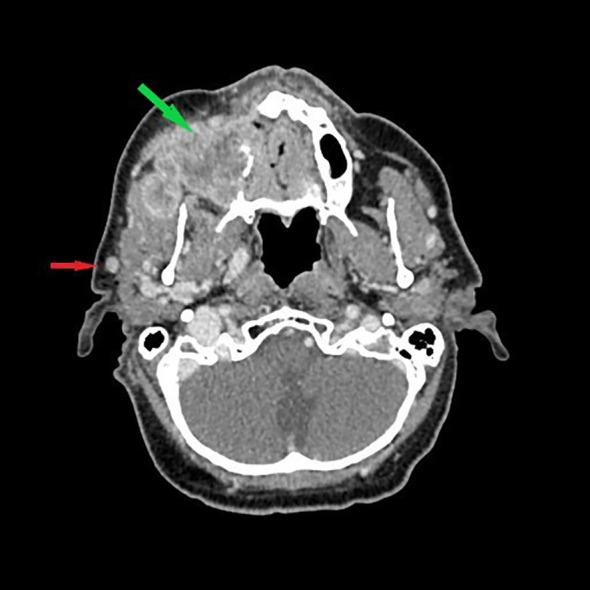

The parotid gland includes lymph nodes that may contain metastasis from the head and neck region as well as distant metastasis or metastasis from carcinoma/melanoma of an unknown primary (CUP/MUP). This study aimed to review the current literature to evaluate the role of surgical management of head and neck squamous cell carcinoma (HNSCC). A narrative review of the English language literature available in the PubMed and Embase databases from January 2010 to December 2024 was conducted to identify treatment methods and follow-up data for HNSCC metastatic to the parotid gland. This study provides a detailed overview of the histological and diagnostic imaging characteristics as well as the surgical and non-surgical procedures employed in the management of HNSCC metastases to the parotid gland. Furthermore, the management of CUP is outlined. The extent of the parotidectomy and concomitant neck dissection remains a topic of ongoing debate. The flow chart presented in this study may assist in decision-making regarding surgical treatment. Given that locoregional recurrence is the primary cause of mortality in HNSCC, surgical treatment is likely to be the most effective means of achieving a favorable outcome.